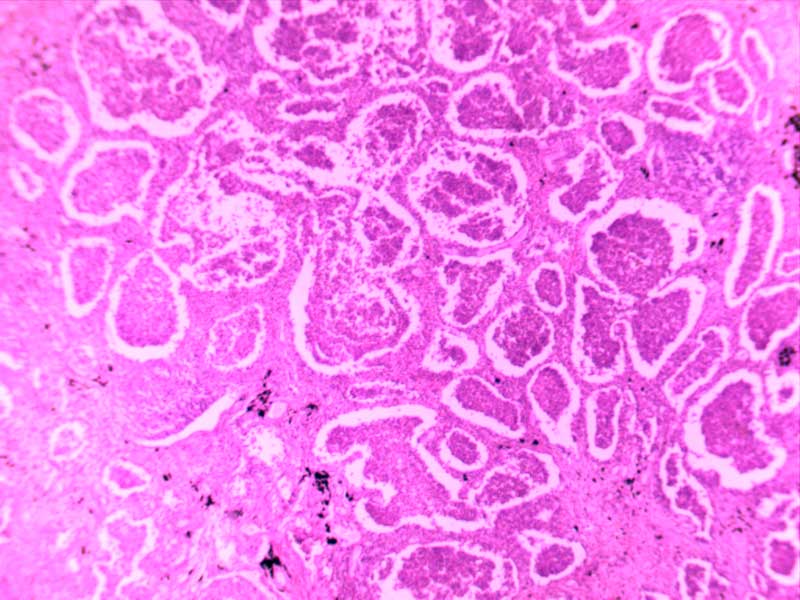

乳头状瘤(膀胱)4倍

乳腺癌-4倍

乳腺癌-10倍

神经鞘瘤4倍